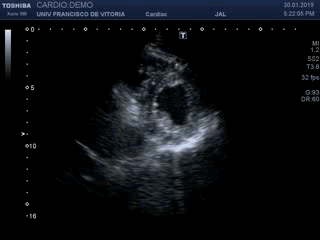

Estas tres próximas imágenes que vas a ver son tres claros ejemplos de lo que es una calcificación grosera de la túnica albugínea, mira:

En estas tres imágenes ves claramente una calcificación grosera, ligeramente curva, que afecta a la túnica albugínea del cuerpo cavernoso izquierdo en su porción interna y profunda. Mide algo menos de 7 mm y esto ya se considera una placa bastante grande. El paciente, por cierto, no cumplía con los estándares de incidencia habitual, tenía menos de 40 años.